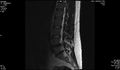

Soubor:Magnetická rezonance bederní páteře.jpg

- Čeština: MR bederní páteře v sagitálním řezu. V etáží L5-S1 je vidět levostranný laterální výhřez plotýnky, která utiskuje nerv.

- Unknown lumbar spine nmr image.

- Author: Tomáš Vendiš